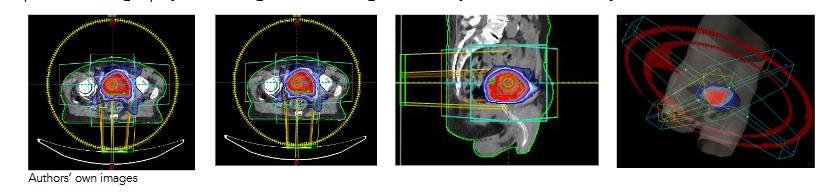

With this apparatus, three scenarios were generated with 1) all plugs inserted, 2) inner plug being out, and 3) no plugs inserted to the Arc Check system. Then, an MLC delivery pattern was selected based on an anonymized patient plan shows in

, which displays a 2 Arcs VMAT plan. In this figure, the dose distributions around the treatment target were showed in 3 different views from a patient computed tomography (CT) image set. The right-side image is a 3-dimensional view. The two Arcs were modulated with the target volume shape. To implement the dose requirement, both delivery aperture and delivery speed were controlled with a complexity of multi-leaf collimator, optimal operation of the gantry rotation and varying dose rate provided by a modern linear accelerator (LINAC), which is a TrueBeam LINAC manufactured by Varian Medical System.